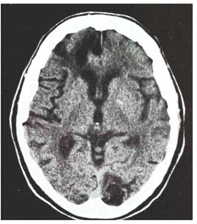

הנזקים המאוחרים של החבלות המוחיות הם: Leukomalacia, אוטמים מוחיים, ציסטות מוחיות, הידרוצפלוס ואטרופיה מוחית, המשאירים נזקים תמידים. הנזקים הללו ניתן להדגמה ב-CT מוח (תצלום 6.16).